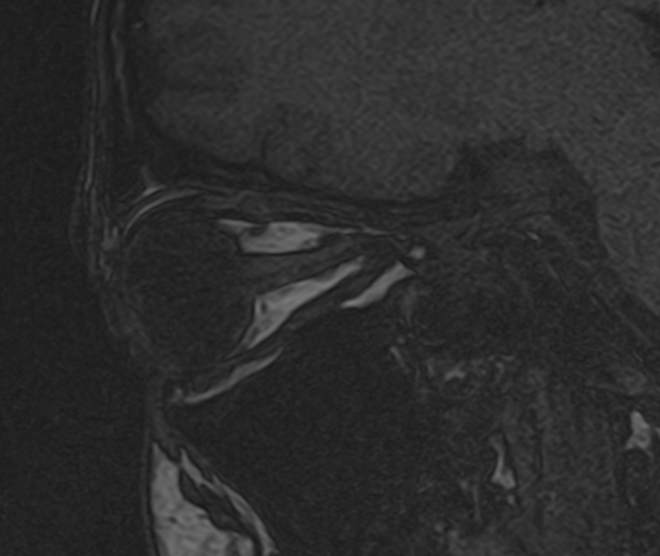

МРТ глазных орбит является современным способом диагностики патологии глазниц, в которых расположены глазные яблоки и их придатки (окружающая жировая клетчатка, зрительные нервы, слезные железы, мышцы глаза, связочный аппарат, кровеносные сосуды). МРТ орбит также позволяет получить детальную информацию о состоянии мягких тканей периорбитальных областей (тканей, окружающих глазницу).

Магнитно-резонансную томографию назначают при необходимости детального изучения мягкотканных структур глазниц. В результате исследования получают срезы анатомической области, на которых можно рассмотреть мельчайшие элементы. МРТ орбит обеспечивает визуализацию следующих структур:

• элементы глазного яблока, включая оболочки;

• периорбитальная клетчатка;

• мышечный аппарат;

• зрительный нерв;

• слезные железы.